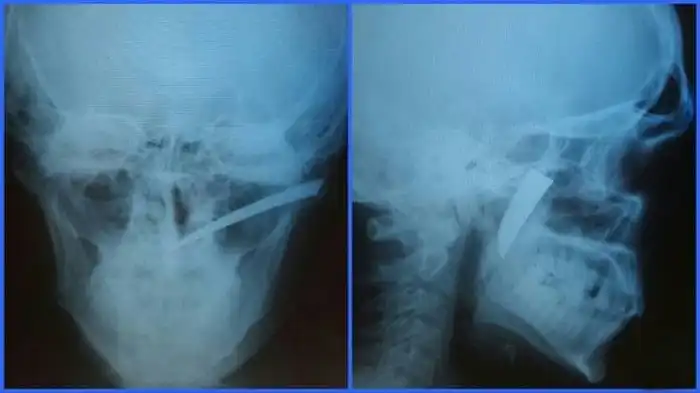

Мужик месяц прожил с ножом в нёбе

Нередко врачи вынуждены извлекать из тел людей самые необычные посторонние предметы, которые не должны были там находиться. В данном случае из мягкого нёба мужчины достали лезвие небольшого ножа, вошедшего под скуловой дугой во время драки. Случилось это за месяц до обращения за медицинской помощью, а беспокоиться пациент начал только потому, что нащупал нечто постороннее в нёбе.